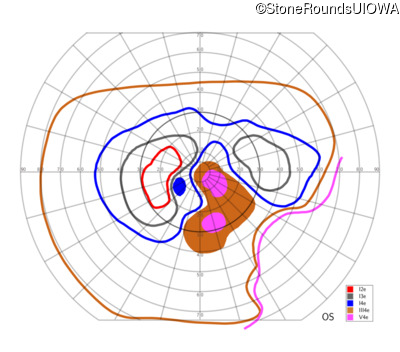

AR Stargardt Disease (IIA)

AR Stargardt Disease (IIA)

| Age at visit: 12 years |

| Age at visit: 13 years |

| Age at visit: 15 years |